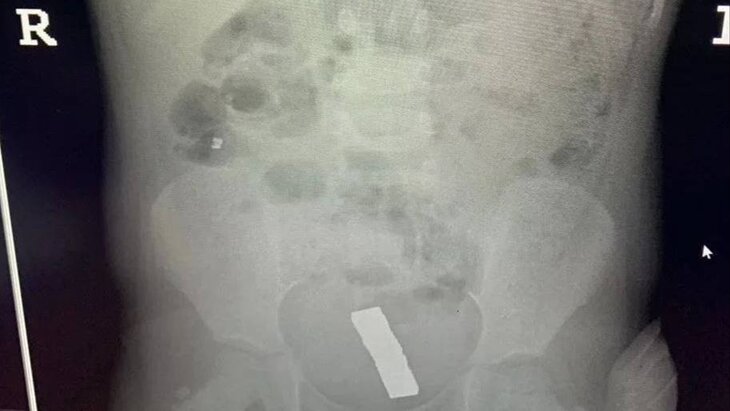

Врачи в подмосковной Балашихе спасли девочку, которая проглотила 20 магнитных шариков. Об этом сообщает телеканал "360" со ссылкой на Минздрав Московской области.

Ребенок поступил в медучреждение с болями в животе. Магниты были обнаружены в кишечнике после обследования.

Юную пациентку направили в детское хирургическое отделение и извлекли шарики в ходе лапароскопической операции через проколы. Для этого медики использовали эндоскоп и специальный инструмент, рассказал заведующий отделением детской хирургии Балашихинской больницы Эмир Жамынчиев.

По его словам, из-за большой силы притяжения магниты образовали в кишке отверстие, которое врачи ушили после их извлечения. Он добавил, что 5 шариков успели переместиться в малый таз.